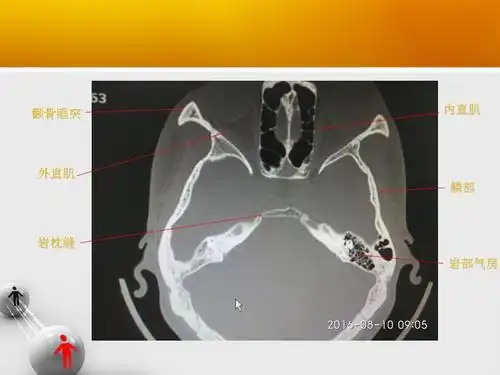

颞骨ct解剖及其常见病变

原创 颞骨断层轴位ct(完整篇)安阳市中医院耳鼻咽喉科

颞骨解剖之ct - 好大夫在线